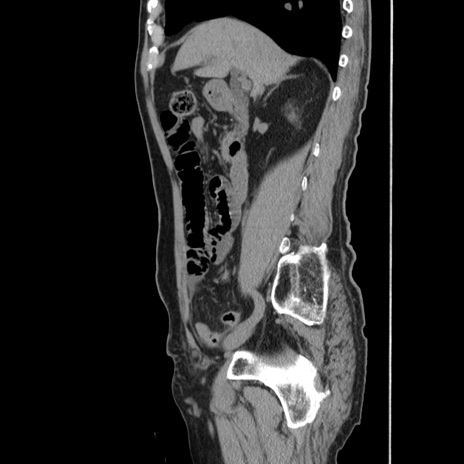

冠状断像

【症例】80歳代男性

【主訴】左側腹部痛、嘔吐

【現病歴】本日早朝より左腹部に痛みあり。昼頃嘔吐認めたため、救急要請。

【既往歴】直腸癌(Mile手術)、胆摘

【身体所見】意識清明、BT 35.9℃、BP 221/93mmHg、SpO2 97%(RA) 、腹部:左ストーマ周囲に限局性の腹部膨隆あり。 膨隆部自発痛・圧痛あり・軟。

【データ】WBC 7700、CRP 0.09